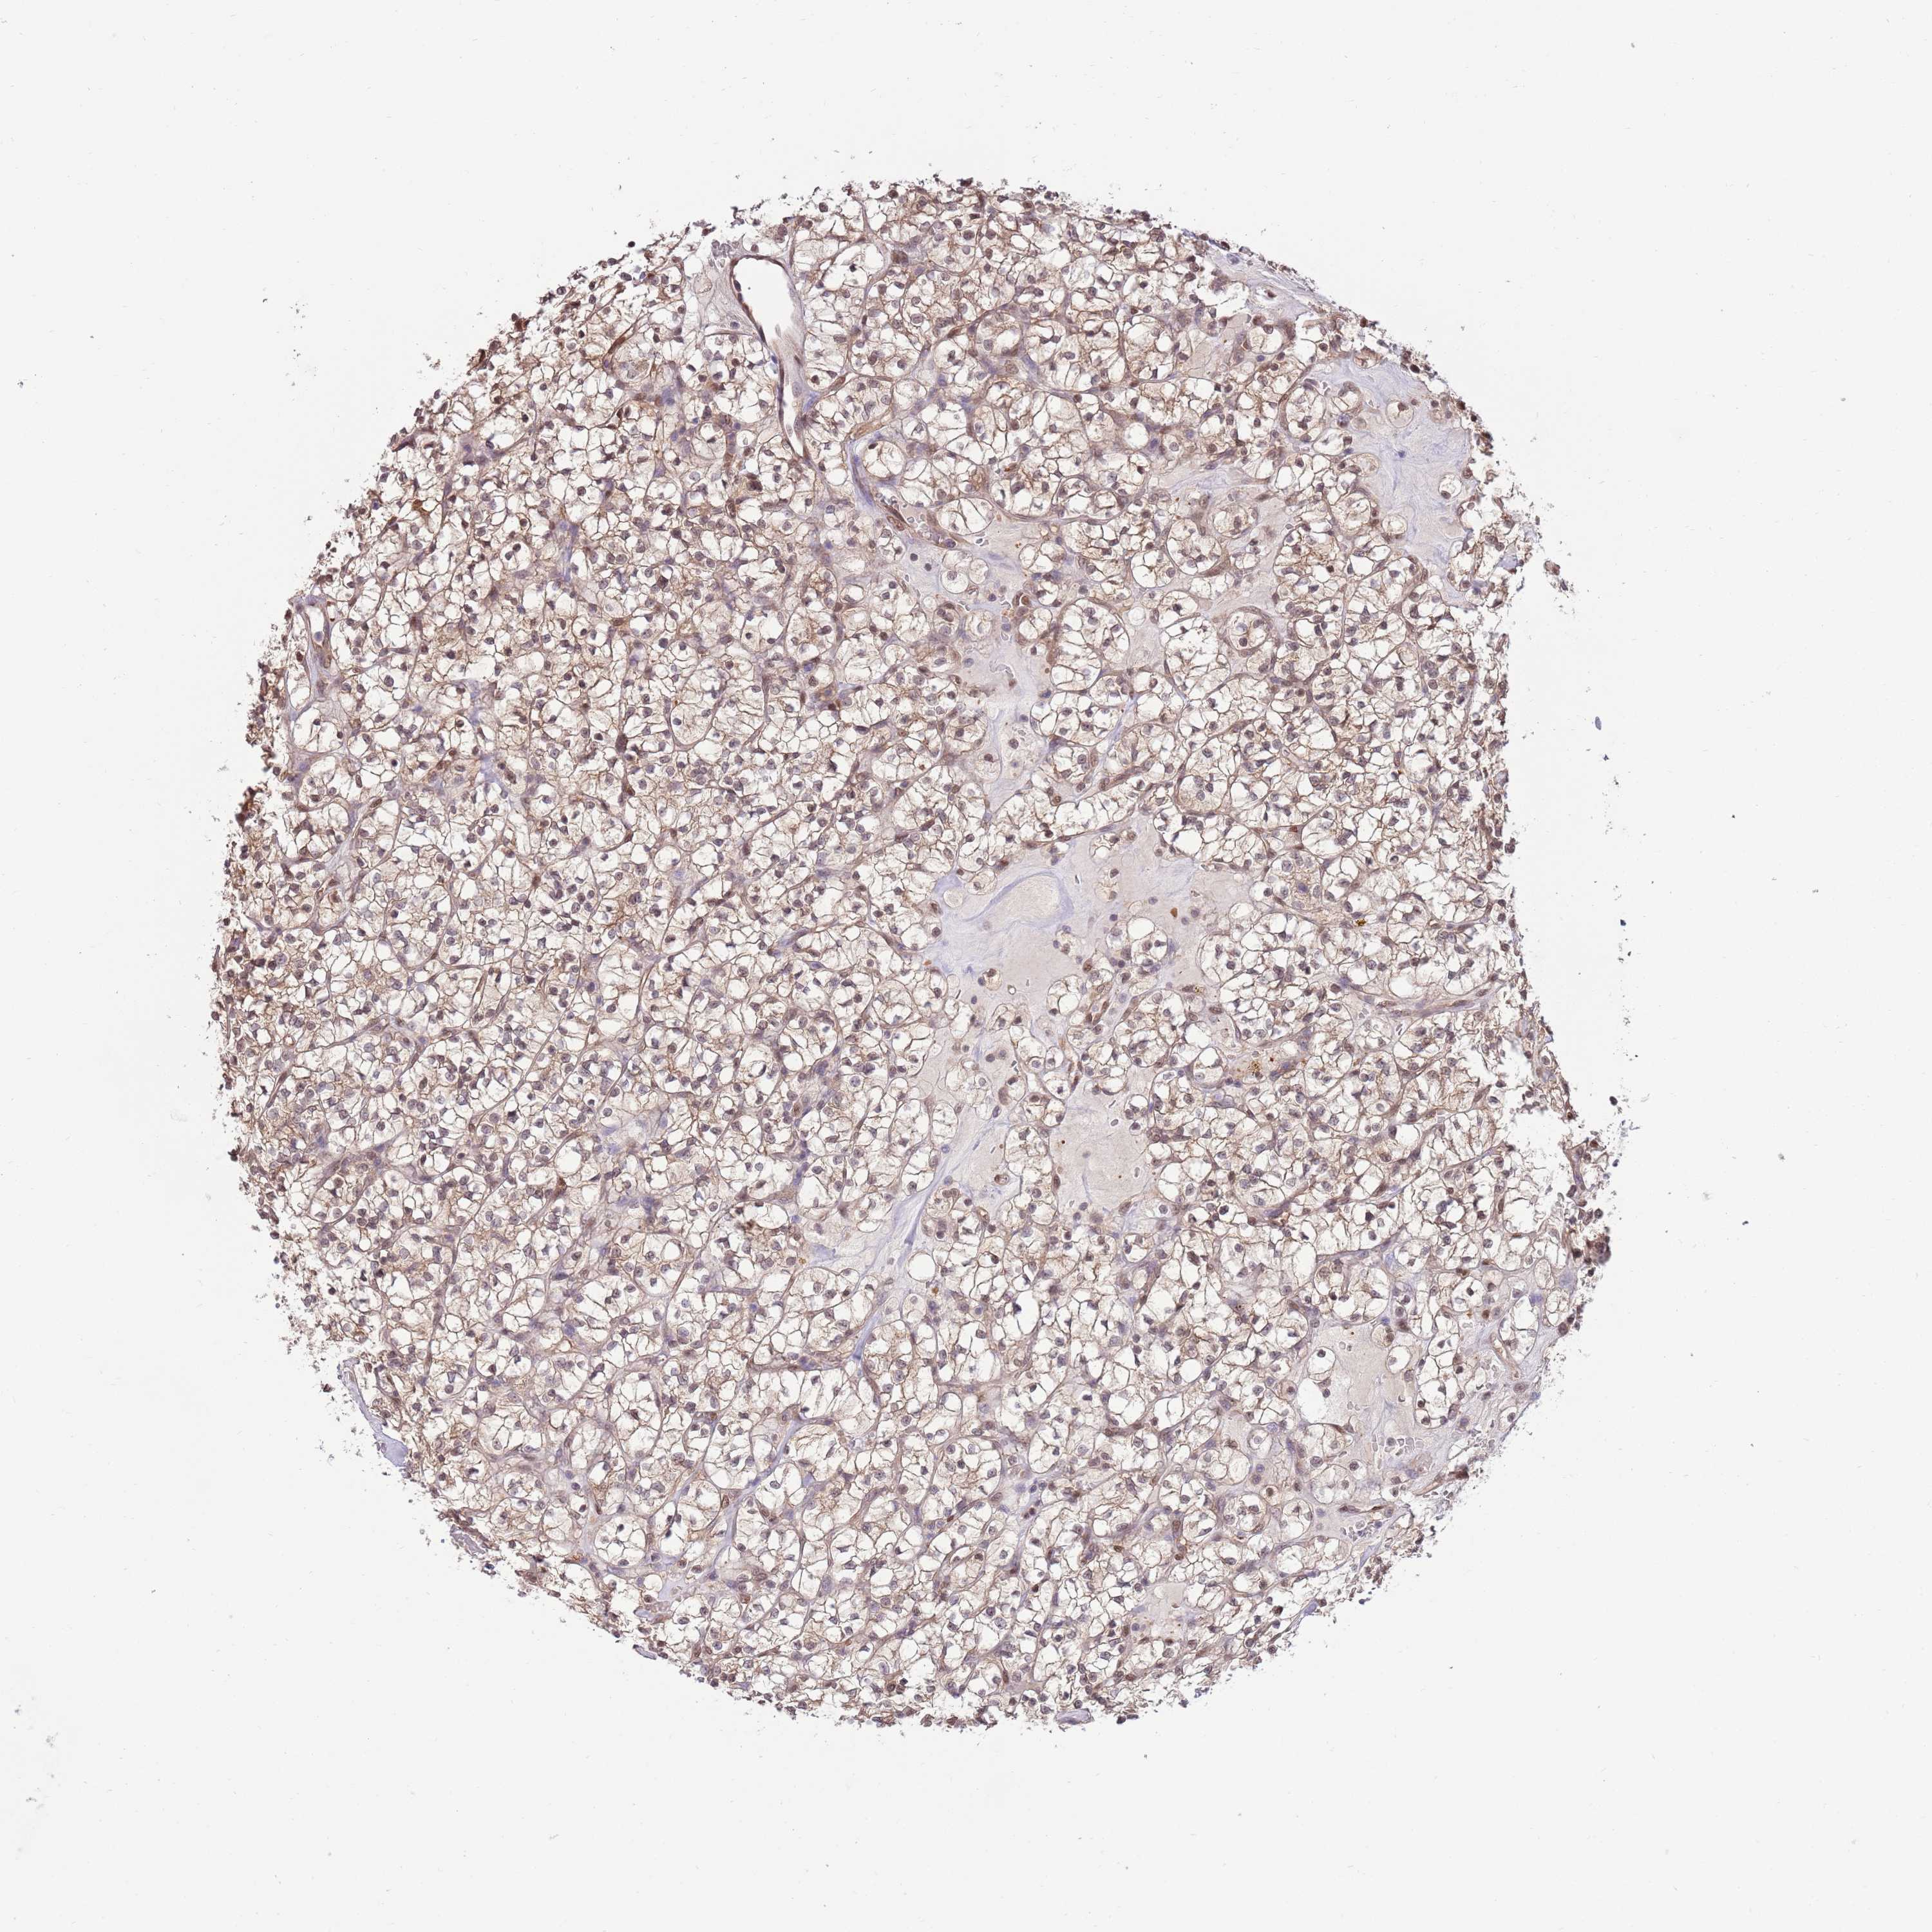

KIDNEY RENAL PAPILLARY CELL CARCINOMA (TCGA) - Interactive survival scatter ploti

The Survival Scatter plot shows the clinical status (i.e. dead or alive) for all individuals in the patient cohort, based on the same data that underlies the corresponding Kaplan-Meier plots. Patients that are alive at last time for follow-up are shown in blue and patients who have died during the study are shown in red.

The x-axis shows the expression levels (FPKM) of the investigated gene in the tumor tissue at the time of diagnosis. The y-axis shows the follow-up time after diagnosis (years). Both axes are complimented with kernel density curves demonstrating the data density over the axes. The top density plot shows the expression levels (FPKM) distribution among dead (red) and alive patients (blue). The right density plot shows the data density of the survived years of dead patients with high and low expression levels respectively, stratified using the cutoff indicated by the vertical dashed line through the Survival Scatter plot. This cutoff is automatically defined based on the FPKM cutoff that minimizes the p-score. The cutoff can be changed by dragging the vertical line or by entering a cutoff value in the square labeled "Current cut-off".

Under the Survival Scatter plot the p-score landscape (black curve; left axis) is shown together with dead median separation (red curve; right axis). Dead median separation is the difference in median mRNA expression between patients who have died with high and low expression, respectively. It is calculated as follows: median FPKM expression of dead patients with high expression - median FPKM expression of dead patients with low expression. This is intended to aid the user in visually exploring custom cutoffs and the associated p-scores and dead median separation.

Individual patient data is displayed and can be filtered by clicking on one or more of the category buttons on the top of the page. Categories describing expression level and patient information include: high, low, alive, dead, female, male and tumor stages. The scale of the x-axis can be toggled between linear and log-scale by clicking on the "x log" button. Mouse-over function shows TCGA ID, patient information and mRNA expression (FPKM) for each patient.

& Survival analysisi

Kaplan-Meier plots summarize results from analysis of correlation between mRNA expression level and patient survival. Patients were divided based on level of expression into one of the two groups "low" (under cut off) or "high" (over cut off). X-axis shows time for survival (years) and y-axis shows the probability of survival, where 1.0 corresponds to 100 percent.

NSFL1C is not prognostic in Kidney Renal Papillary Cell Carcinoma (TCGA)